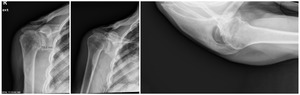

Case two is an 86-year-old female with long standing left shoulder pain and loss of function. Preoperative exam shows 70° of active forward flexion, neutral external rotation, and internal rotation to the lateral thigh. Radiographs (Figure 5) and CT scan (Figure 6) show significant posterior bone loss and retroversion with medialization of the joint line. Options include asymmetric reaming, an augmented component, or bone grafting. An augmented reverse baseplate was selected for this elderly female. Radiographs at six months show a well fixated baseplate with improvement of the pre-operative retroversion (Figure 7).